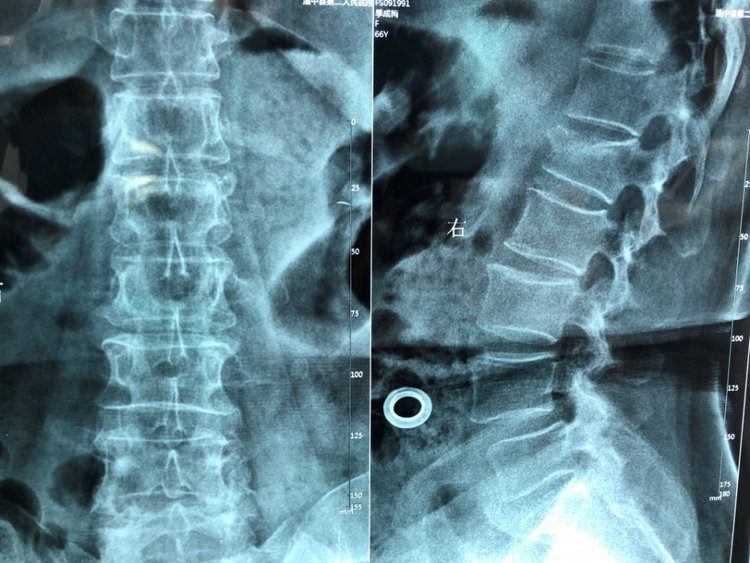

一位89岁女性,在家走路时不小心摔倒了,立刻感到腰背部疼痛,甚至影响站立和行走了,在自行休息后,仍然感觉疼痛没有好转,于是在家人的劝说下,来郑州大学五附院就诊。急诊科医师立即完善了CT检查,提示胸12及腰1椎体骨折,为了进一步治疗,来骨科一病区住院。

住院后骨科医生立即完善了MRI检查,发现胸12椎体为陈旧性压缩骨折,腰1椎体为新鲜压缩性骨折,在完善各项生化检查、心电图等检查的基础上,评估患者体质后,建议患者进行微创手术:经皮穿刺腰1椎体骨水泥成形术,这样患者能够快速康复、提高生活质量、减少并发症发生率,与患者及家属充分沟通病情及治疗建议后,患者及家属一致决定接受我们的建议。

胸腰椎压缩性骨折多发于下胸椎和上腰椎,有时不一定合并外伤史。患者主诉腰背痛,不敢活动,可妨碍站立行走。如果压缩程度较重,将会产生局部后凸畸形。压痛叩击痛常见,胸腰椎活动受限。胸腰椎压缩性骨折大部分为稳定骨折,少有脊髓损伤瘫痪者。X线或CT即可发现压缩骨折,但要确定是否为新鲜骨折,需再进行MRI检查。